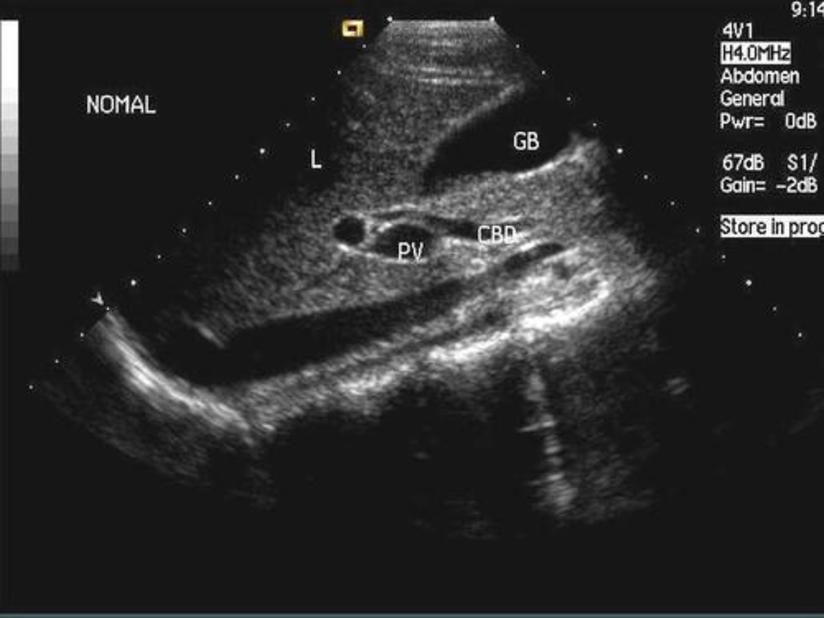

Aug 25, · 胆囊炎最主要的一 个症状就是吃了油腻的食物后会感觉到右上腹不舒服或者疼 。如果炎症厉害的话还会出现发烧 ,白细胞升高等 。甚至有更严重的表现。所以最主要的要靠影像学诊断 ,看看胆 囊里面有没有石头。急性胆囊炎为急性胆囊炎症,是胆石病或胆结石的主要并发症之一。高达 10% 的症状性胆结石患者进展为急性胆囊炎。 Ziessman HA Acute cholecystitis, biliary obstruction and biliary leakage胆囊炎是一种比较常见的消化道疾病,根据起病的缓急可以分为急性胆囊炎和慢性胆囊炎,常常并发于胆囊结石后发生。 由于胆道梗阻,胆道淤积造成感染,一旦起病,发展迅速。 部分患者可能无胆囊结石时发病,存在发热、腹痛等临床症状,需以药物和手术相结合进行个性化治疗。 就诊科室 消化内科、肝胆外科 是否医保 是 英文名称 cholecystitis

右上腹痛的疾病很多 怎么确定是不是胆囊炎 一项检查就可以 腾讯新闻